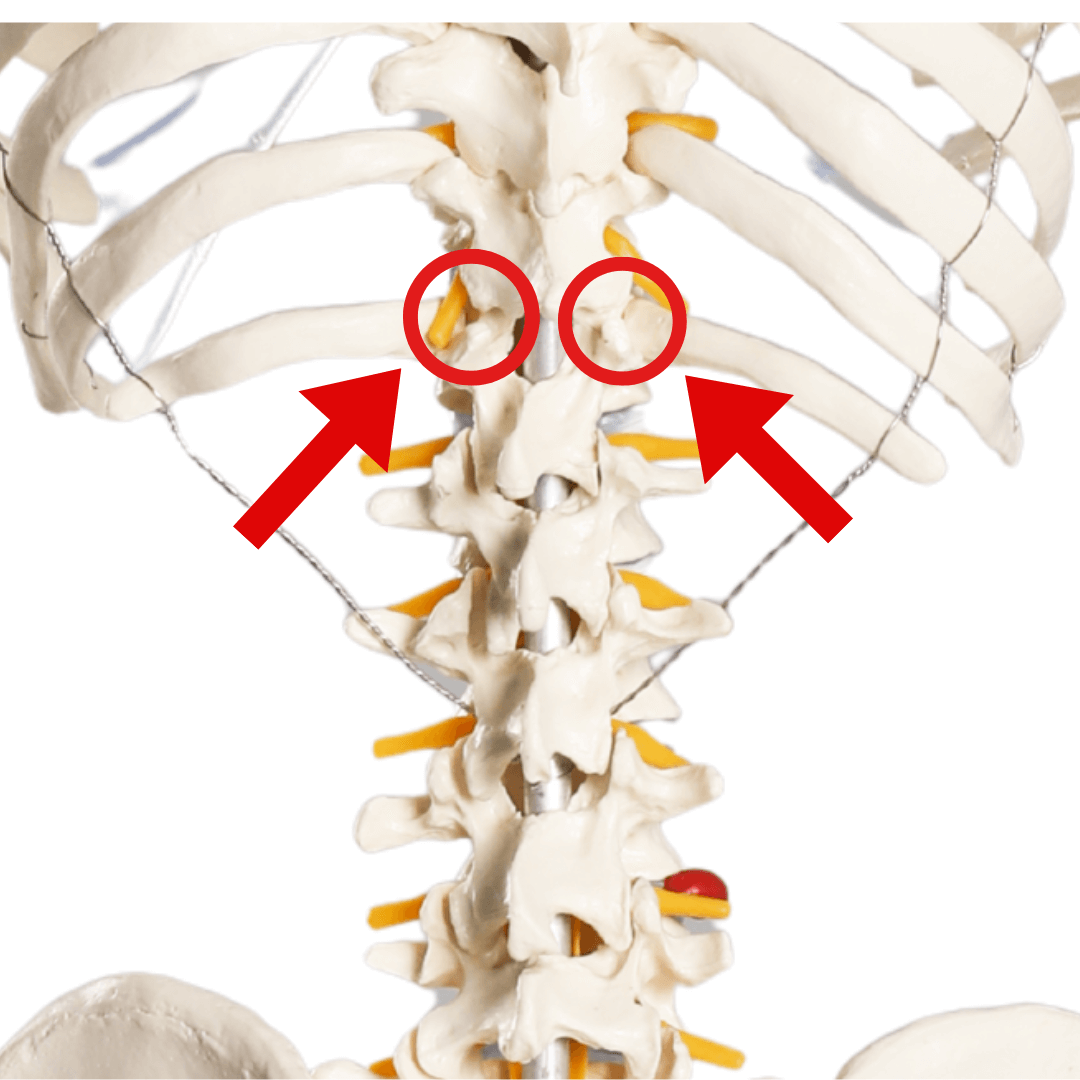

腰仙関節(L5-S1)の可動不全

腰仙関節(腰椎5番と仙骨の間)が、背骨で可動が大きい関節なのですが、最も見落とされやすいのです。

前屈       後屈

正常な可動域    13度        8度

障害がある時    4〜6     2〜3

この関節は、上半身と下半身をつなぐ最重要ポイント。

体重の70%がこの一点に集中し、歩くたびに体重の3倍の負荷がかかります。

実は「変形性膝関節症」の方の99%が、腰仙関節の問題を抱えています

胸椎の関節の可動不全

特に11~12番の関節は、胸椎と腰椎の切り替わり部分で体重がかかる場所です。

この関節が固まると、膝が伸びなくなります。

正常な可動域     4~6度     4~6度

狭窄症患者     1度以下      1度以下

多くの施術院は膝だけを診ますが、実は胸椎の問題こそが、変形性膝関節症「隠れた黒幕」なのです。